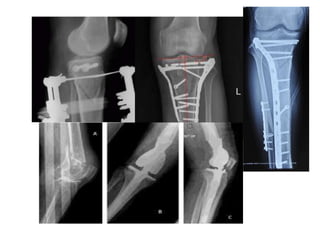

Operative treatment

Accepted range of articular

depression varies from < 2 mm

to 1 cm – Instability > 10

degrees of nearly extended

knee compared to the

contralateral side – Open

fractures – Associated

compartment syndrome –

Associated vascular injury

Goals of treatment: –

reconstruction of the articular

surface – re-establishment of

tibial alignment • Treatment

involves reducing and

buttressing of elevated articular

segments with bone graft • Soft

tissue reconstruction including

menisci and ligaments •

Spanning external fixator as a

temporizing measure in

patients with high-energy

injuries or significant soft

tissue injury. • Arthroscopy

• 42.

Operative treatment Accepted rangeof articular depression varies from < 2 mm to 1 cm – Instability > 10 degrees of nearly extended knee compared to the contralateral side – Open fractures – Associated compartment syndrome – Associated vascular injury Goals of treatment: – reconstruction of the articular surface – re-establishment of tibial alignment • Treatment involves reducing and buttressing of elevated articular segments with bone graft • Soft tissue reconstruction including menisci and ligaments • Spanning external fixator as a temporizing measure in patients with high-energy injuries or significant soft tissue injury. • Arthroscopy